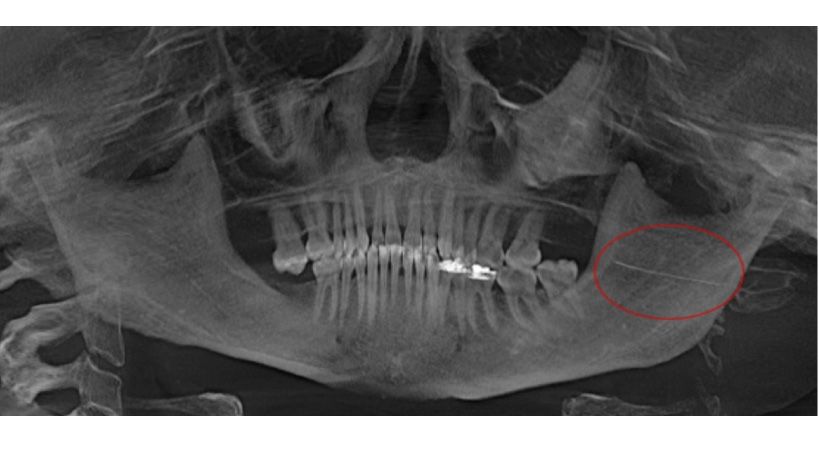

Objetivo: presentar un caso clínico, en el cual, durante la extracción quirúrgica de una aguja fracturada, en el período transoperatorio, el paciente sufre síncope vasovagal, con un aumento marcado de la tensión arterial (179/119 mmHg).